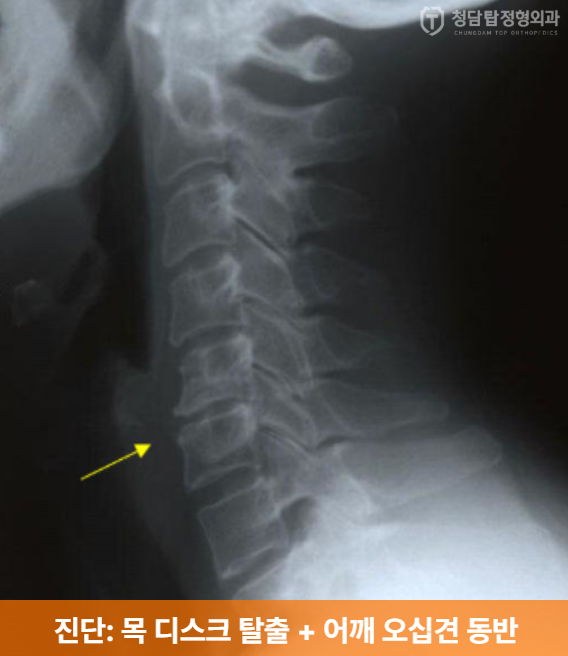

위 증상들을 듣고, x-ray를 분석해본 결과,

경추 추간판 탈출증(목 디스크)과

유착성 관절낭염(오십견)이 동반된 복합적인 상태로 최종 진단되었습니다.